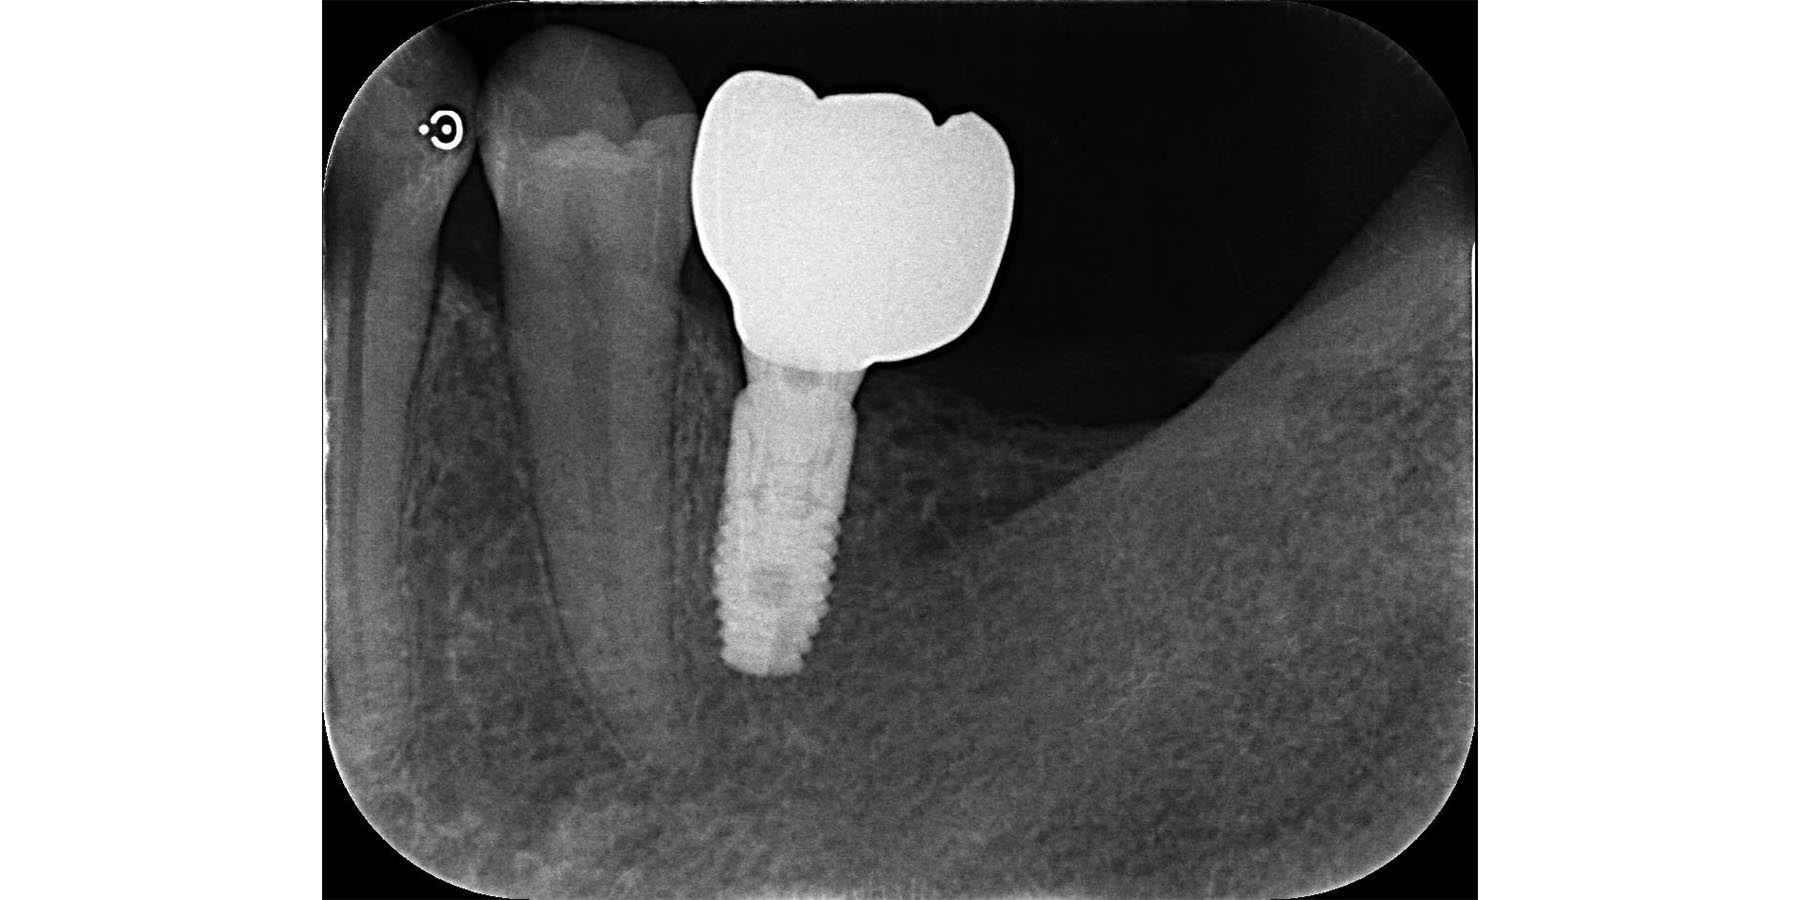

被せ物セット完了

| 治療内容 | 麻酔科認定医による静脈内鎮静下で 左右下顎6のインプラント治療(2本) |